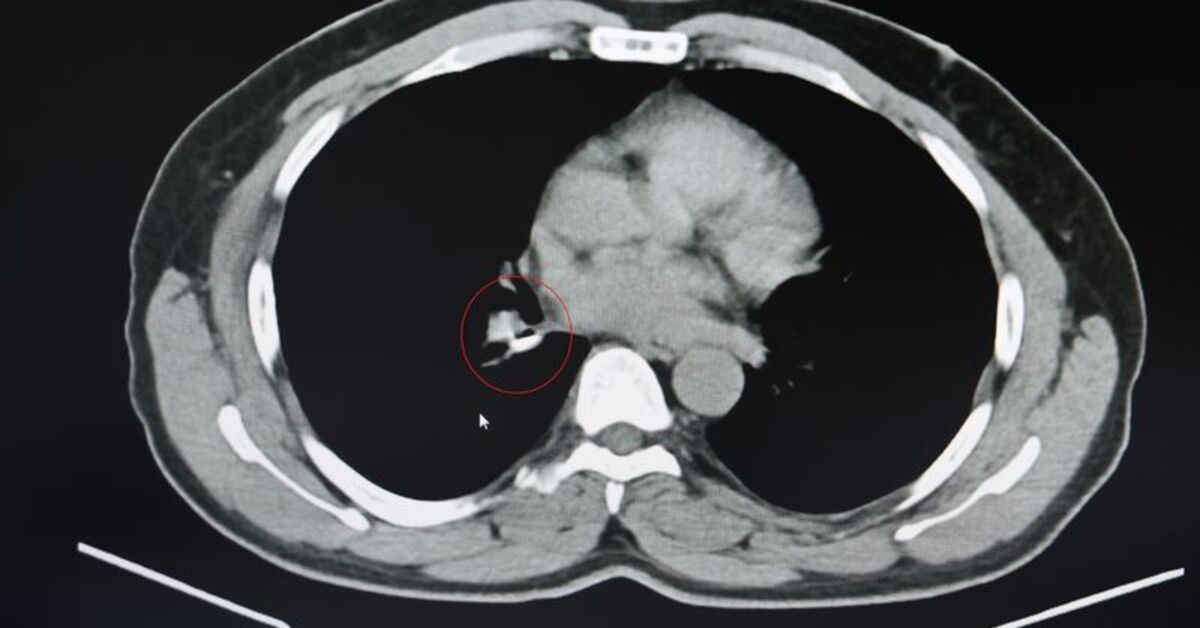

1.5 yıldır astım tanısından sonra tedaviler almaya başlayan İ.U., Prof. Dr. Abdurrahman Şenyiğit’in yanına geldiğinde yapılan tetkiklerde gerçek bambaşka çıktı. Yapılan tomografi ve bronskokopi işlemlerinde akciğere yerleşen maddenin yutulan silikon olduğu belirlendi. Silikonun çıkartılmasıyla hastanın şikayetlerinin ortadan kalktığı belirtildi.

Şenyiğit, o maddenin zamanla akciğer yapısının özelliğini aldığını ve orada yabancı bir madde olarak kaldığına değinerek, “Hastamıza maalesef 2 yıldan beri astım tanısı konulmuş ve sürekli tedavi verilmiştir. Hasta bize geldiği zaman yapılan tomografide sağ akciğer ana bronşun distalinde şüpheli lezyon gördük. Uyguladığımız bronskokopide yabancı maddenin silikon olduğunu tespit ettik. Onu çıkardıktan sonra da hastada bir rahatlama meydana geldi” dedi.